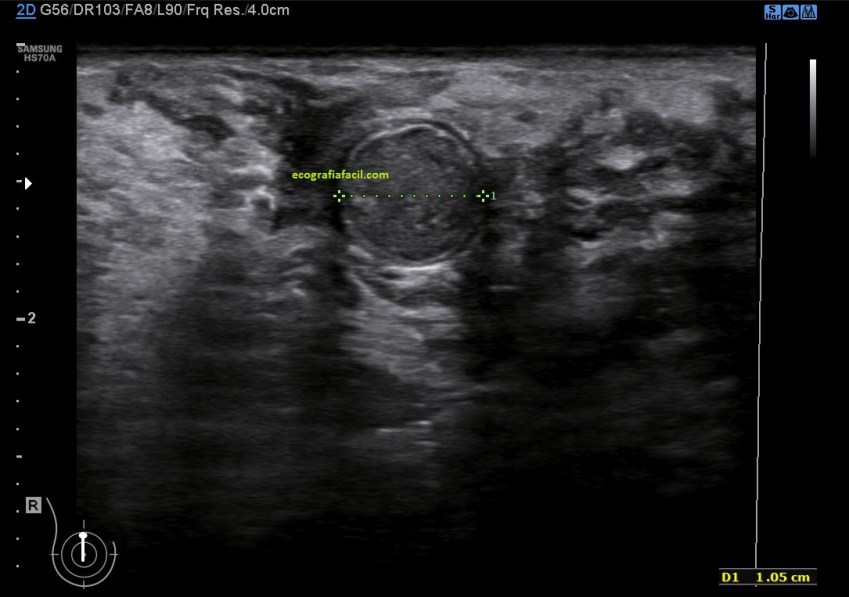

La mayoría de los quistes suelen ser como los descritos anteriormente, anecoicos, bordes lisos, ovalados, con refuerzo posterior,imagen 3,pero hay muchos tipos, te enseño algunos…»preciosos», mira: